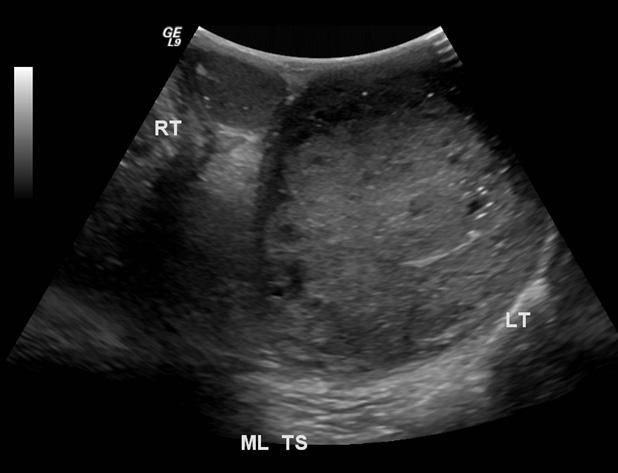

The most common form of fusion anomaly of the kidneys

Horseshoe Kidneys

The most common form of fusion anomaly of the kidneys

Horseshoe Kidneys